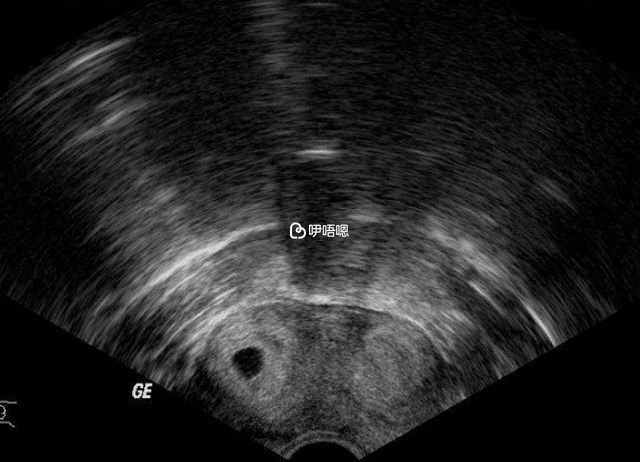

雙角子宮是什麼意思?顧名思義子宮左右各有一個角,主要是在胚胎髮育時期子宮底的部分匯合不全,導致形成了一個宮頸及一個陰道1,由於從形狀上來看,發現子宮兩側各有一角突出,故稱為雙角子宮。

根據畸形程度的不同,還會形成所謂馬鞍形子宮、心形子宮、弓形子宮,一般情況下40%的雙角子宮患者會出現流產、早產、分娩異常或不孕不育症等。